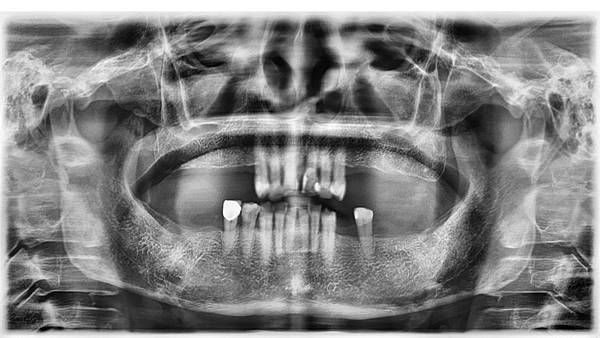

牙周病全口重建病例3

牙周病全口重建病例2

牙周病全口重建病例1

即時拔牙即時植牙病例2

即時拔牙即時植牙病例